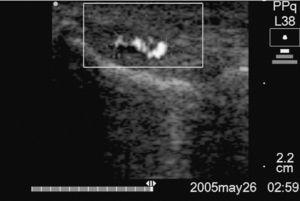

Cas 1. Nombre de sessions: 2; satisfacció del pacient: Sí; efectes adversos: No; vasos abans: +3; vasos després: +1; escala analògica visual [VAS] abans: 90; escala VAS després: 10; retorn laboral (figures 2a i b).

Figura 2b Tall longitudinal del tendó de la figura 2A que, després de 2 sessions esclerosants i exercicis excèntrics, va mostrar una neovascularització +1.